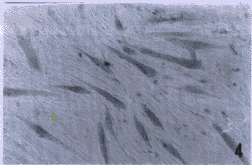

用脂质体Lipofectin介导转染新构建的pCMVTHC后,继续培养48~72h,所有原代培养肌细胞分化成肌管细胞。它们中间30%~40%细胞免疫组织化学染色呈棕色,提示有THC序列的表达(图5),未转染上外源基因的肌管细胞在同一张片子上呈淡粉色(本底)。

图5 用含TH催化核心序列的pCMVTHC转染骨骼肌细胞,进行免疫组织化学染色后,表达THC序列的细胞呈棕色

Fig.5 The cultured muscle cells were transfected by plasmid pCMVTHC.The cells appeared brown showing THC expression with immunohistochemical staining.